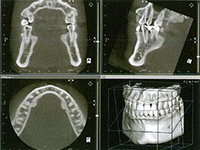

検査後、緻密な治療計画

インプラント治療を始める前には、慎重な事前検査が必要になります。レントゲン撮影・CTスキャン・口腔内模型などによる十分な検査を行い、綿密な治療計画を立てます。患者さんの同意を得てから手術の日程を決めます。